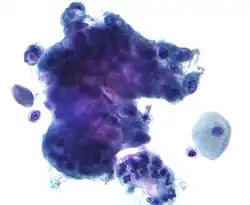

The endocervical mucosa is a site from which adenocarcinoma can arise. Endocervical adenocarcinoma, like cervical cancer (squamous cell carcinoma), often arises in the milieu of human papillomavirus infection.[3]

As most endometrial cancers are adenocarcinomas, differentiation of endocervical adenocarcinoma and endometrial adenocarcinomas is required, as the treatment differs. Immunohistochemical staining is often helpful in this regard, endocervical adenocarcinomas are typically CEA and p16 positive and estrogen receptor, progesterone receptor and vimentin negative.